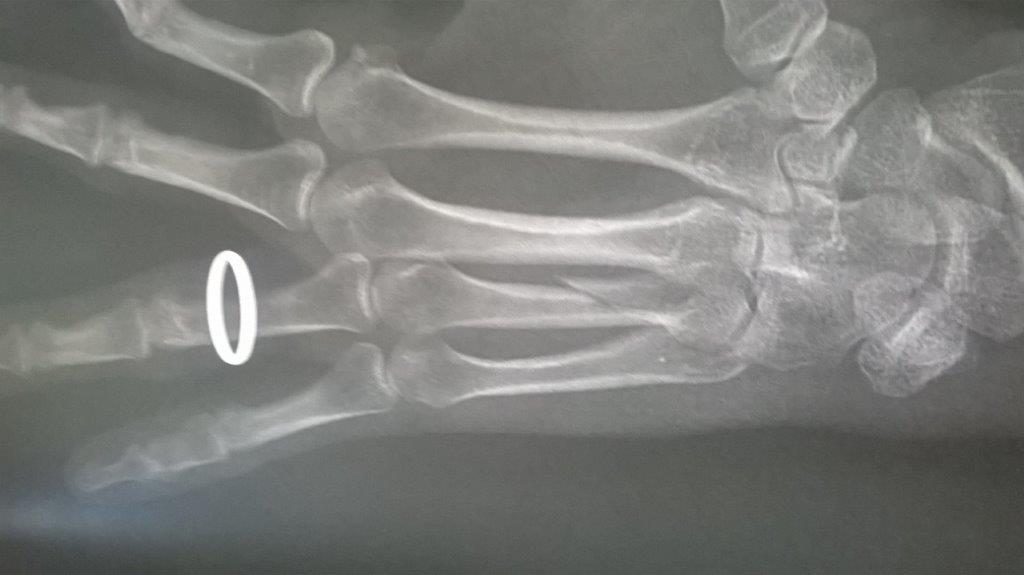

Résultat : fracture de la main gauche

Fichier(s) joint(s):

WP_20170914_001.jpg [ 47.5 Kio | Vu 29224 fois ]

Mais je confirme que ma saison de triathlon s'achève aujourd'hui. Main gauche immobilisé. Je suis au regret de déclarer forfait pour Paladru et d'abandonner les Mixirilliettes à leur triste sort